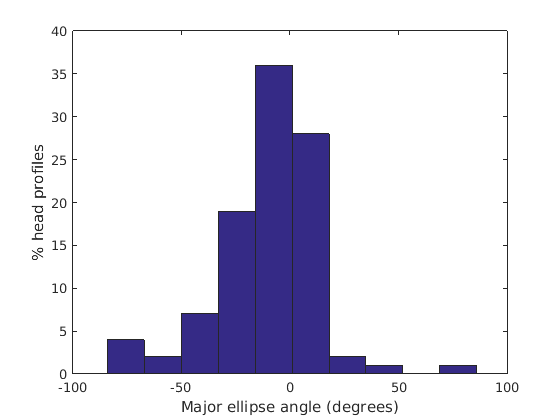

Figure 17 shows all 100 profiles overlaid with the same alignment scheme. The median value of major ellipse axis and the ellipse centre-nasion angle differ by 3.6 degrees, so that when the nasion angle is fixed at -10 degrees, the median ellipse angle is -6.4 degrees (cf. -7.4 degrees with manual landmarking of the nasion). We noted regularity in the orientation of the fitted ellipse as is indicated by the clustering of the major (red) and minor (green) axes in Fig. 17 and the histogram of ellipse orientations in Fig. 18. For most people, the major axis of the ellipse is closely aligned with the y-axis (upright), and titled slightly forwards. A minority of heads (9%) in the training sample have their major ellipse axes closer to the vertical (these relatively tall and short heads are known as brachycephalic.) Ellipse axis clustering (relative to the fixed ellipse centre-nasion line) does not appear to be sharply defined. This is because many crania are close to circular in cross-section, making the orientation of these angles sensitive to small changes in shape from one person to the next. Note also the variation at the back of the head due to a variety of hair styles, some of which protrude from under the cap. We limit the region over which we model the cranial shape in order to crop this unwanted data out.